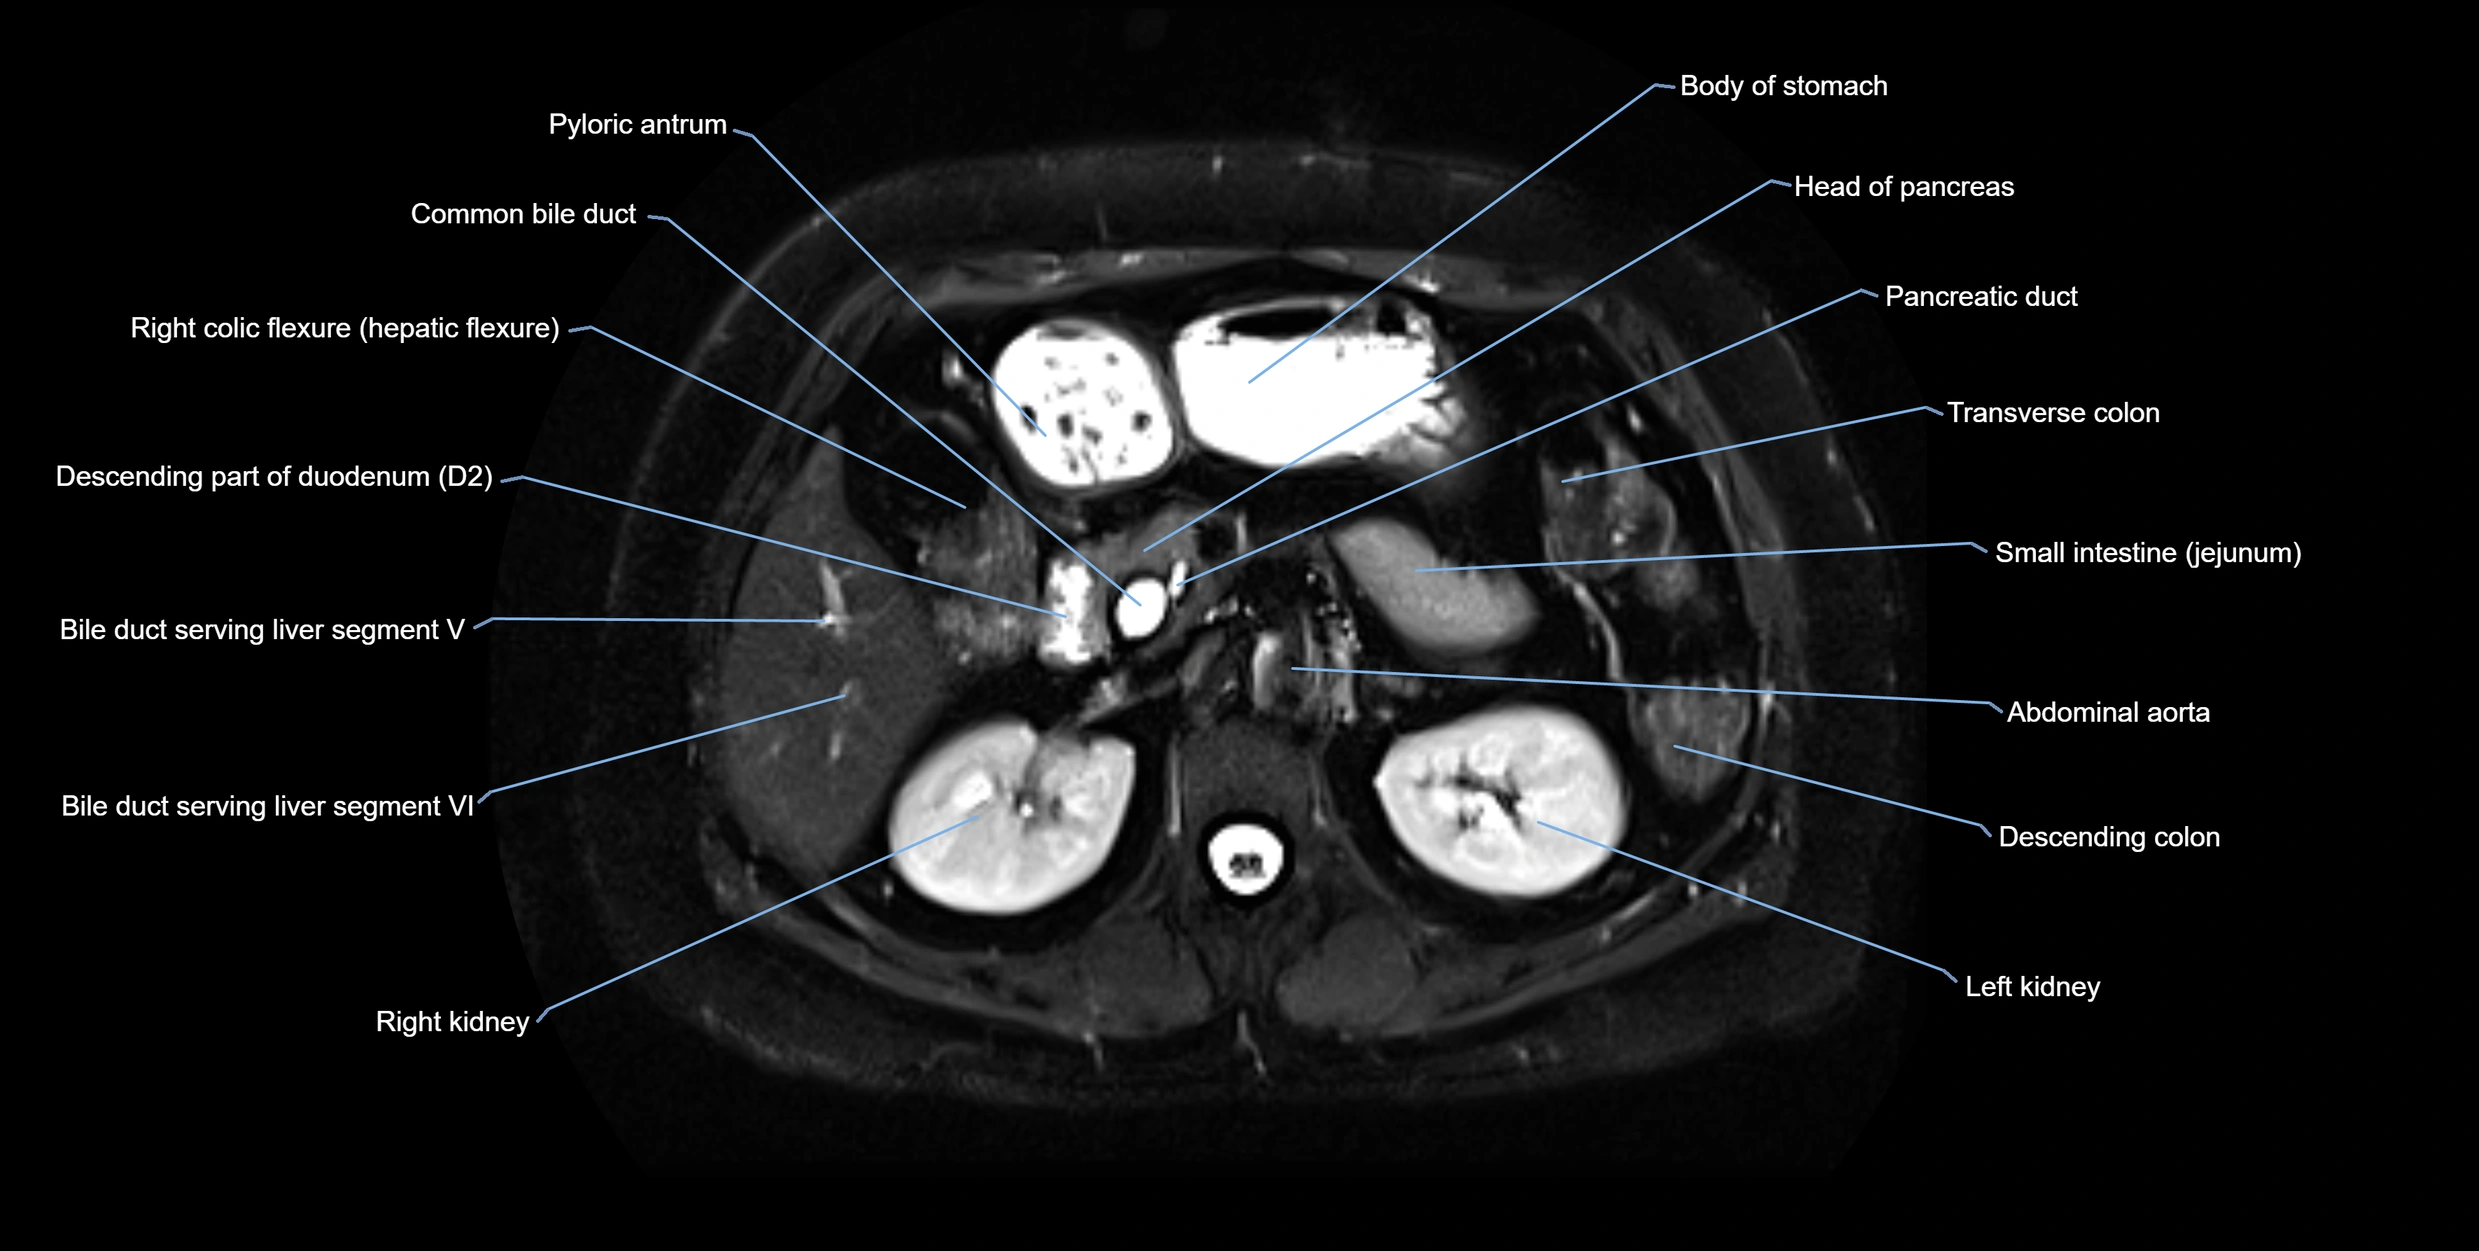

MRI image

image